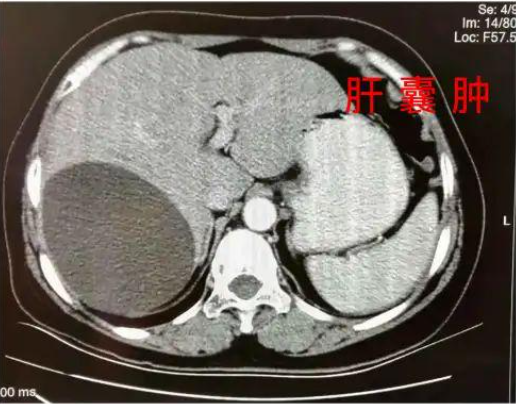

谁能想到,她从小就是个“药匣子”,因为早产,天生体弱,再加上营养不良,身体抵抗力极差,感冒、发烧、肺炎,是家常便饭,呆在病房的时间比在学校都要长。那时候流行输液,她胳膊上,脚上都扎满了针孔,后来没地方扎针,就从头皮输液!各种抗生素和白药片几乎成了下饭菜,父母担心她的身体,经常夜里叹气、流眼泪。大学毕业后,通过打拼,条件改善了,但是由于身体基础差,又患上了肝囊肿,卵巢囊肿等疾病。工作时候,由于过于拼命,多次晕倒被120抢救!为了治病,李泓霖只能不断吃药,这也导致肝损伤加重。被折磨的太久了,甚至想过放弃治疗。一次偶然的机会,她接触到了世界自然医学会联合总会主席马永华教授的讲座,了解了营养食疗,让她意识到,只要注意调养,调理好肝损伤,就能重塑代谢系统,80%的疾病都能够自愈。从此,李泓霖老师就踏上了打磨饮食调理法的道路,而她就是第一位试验者和受益者。当她为自己调理了半年后,去体检,医生告诉她可以把药都停了。当时医生都不相信坚持结果,把护士喊来反复确认了好几次!从此,李泓霖老师决定把这套方法造福更多人,她还考取了国家一级营养师和国际注册营养师,成为国家第一批营养师。由于李老师用自愈力饮食法帮很多病人调理好了身体,李老师的名声也越传越开。后来她主持开办了北大营养班,邀请国内外营养学专家前来讲学,随后开始全国巡讲。在全国巡讲时,她经常会被问到关于如何降三高,溶解斑块的问题。其实,这些都只能通过饮食调理,科学饮食修复肝损伤,唤起自愈力,可以调百病↓李泓霖老师对比了东西方近百种饮食方法,发现国外虽然也有不少好的饮食法,但是和国人的体质和生活环境不是很匹配,为了打磨更适合国人的营养食疗体系,李老师把营养科学和中医结合了起来,并根据国人的身体情况和饮食、养生习惯,联合长轻,研发出了一套4816营养食疗法。这方法是否有效呢?老师的咨询一天比一天人多,火爆的时候,一场直播有数万人同时在线,反馈好评满满,就是最好的证明。